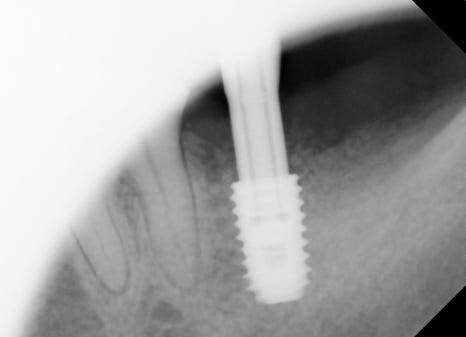

Recovery and second surgery process

After implant placement, time is needed for the bone and implant to

integrate.

After about 2 to 3 months, a second surgery is performed

to connect the implant above the gums.